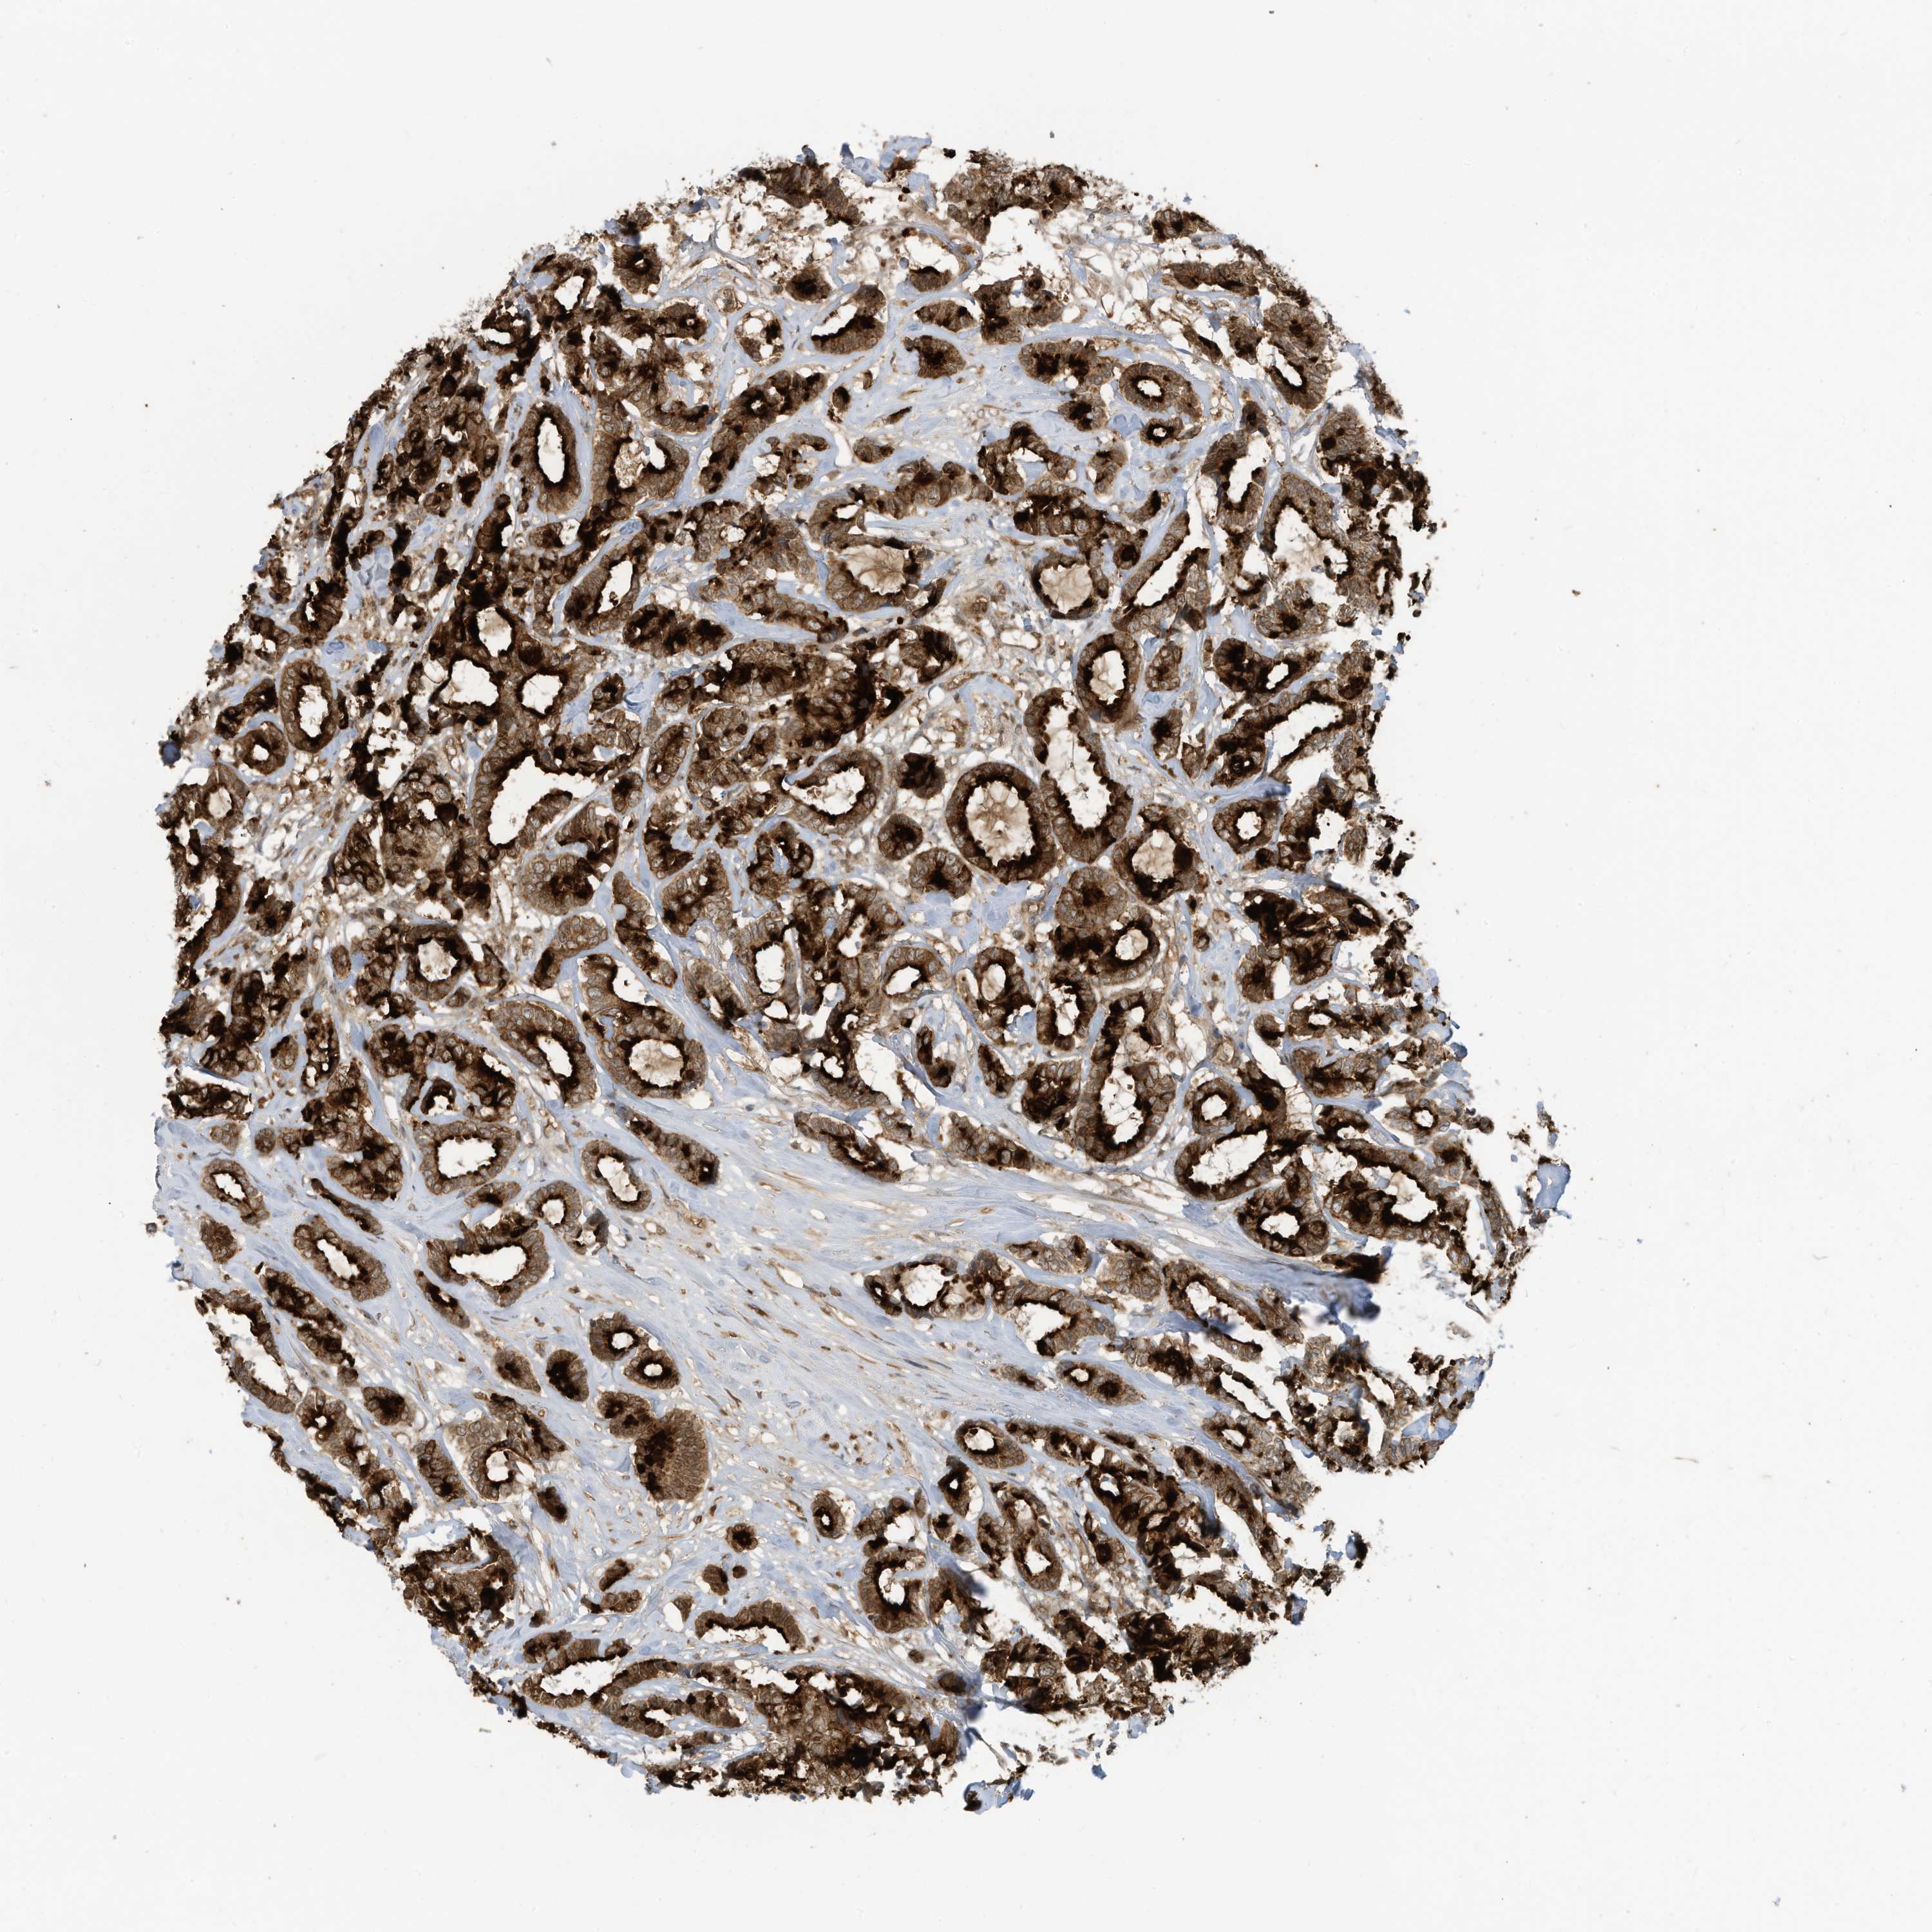

CANCER BREAST CANCER Show tissue menu

BRCA TCGA BRCA VALIDATION PROTEIN EXPRESSION